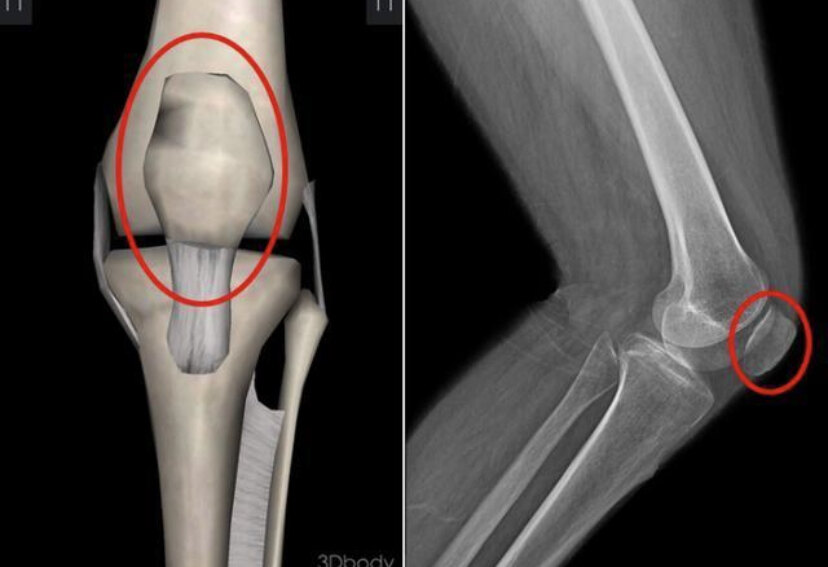

1.踢球为何容易受伤

踢球是一项激烈的运动,常常会导致膝盖受伤。这是因为在踢球过程中,膝盖承受着巨大的压力和扭力,容易受到外力的冲击。而且,由于踢球时需要频繁转身、急停、跳跃等动作,这些运动对膝关节的稳定性要求很高,稍有不慎就可能造成损伤。